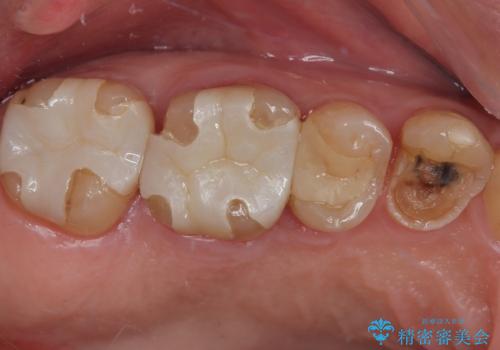

- 食事中に歯が欠けてしまった事を主訴に来院された患者様です。

小臼歯が広範囲に欠けてしまっています。

部分的な詰め物では再びかけてしまうリスクが高いため、オールセラミッククランにて補綴治療をすることとしました。